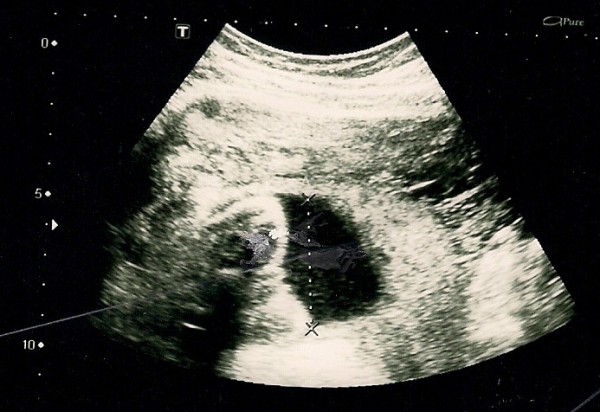

산부인과 초음파는 태아의 크기로 임신 주수를 측정하고, 태아의 수와 태반을 확인하며, 자궁외 임신과 임신 초기 출혈을 평가하는 데 일상적으로 사용된다. 태아의 성장이 다른 요인에 의해 크게 영향을 받기 전인 임신 초기, 특히 첫 번째 삼분기에 가장 정확하게 측정된다.[22] 초음파는 또한 선천적 기형(또는 기타 태아 기형)을 감지하고 생물리학적 프로파일 (BPP)을 결정하는 데 사용되며, 태아 구조가 더 크고 발달된 임신 두 번째 삼분기에 일반적으로 더 쉽게 감지할 수 있다.[23]

X-선 및 전산화 단층 촬영 (CT)은 특히 임신 초기에는 이온화 방사선으로 인해 사용되지 않으며, 이는 태아에게 기형 발생 효과가 있다.[24] 자기 공명 영상 (MRI)이 태아에게 미치는 영향은 입증되지 않았지만,[25] 이 기술은 일상적인 관찰에는 너무 비싸다. 대신, 산부인과 초음파는 방사선을 방출하지 않고 휴대 가능하며 실시간 영상을 허용하므로 임신 초기 및 임신 기간 동안 선택되는 영상 방법이다.[26]

잦은 초음파 검사의 안전성은 확인되지 않았다. 그럼에도 불구하고, 성별 스캔, 3D 및 4D 스캔과 같이 의료적 목적 없이 추가 스캔을 선택하는 여성의 수가 증가하고 있다.[27] 정상적인 임신에서는 임신 낭, 난황 낭, 태아 극이 나타난다.[28]

임신 주수는 6주차 이전에는 평균 임신 낭 직경(MGD)을 평가하고, 6주차 이후에는 머리-엉덩이 길이(crown-rump length)를 평가하여 측정할 수 있다. 다태 임신은 존재하는 태반과 양막의 수로 평가된다.[29]